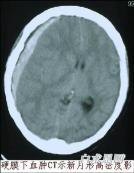

慢性硬脑膜下血肿

628健康网为您分享有关慢性硬脑膜下血肿的症状,慢性硬脑膜下血肿的治疗方法,慢性硬脑膜下血肿的预防知识,慢性硬脑膜下血...